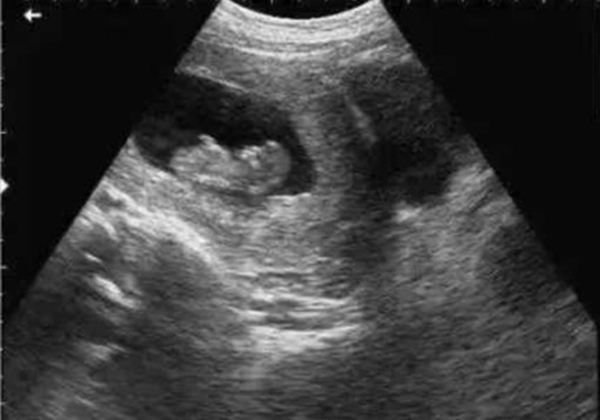

? 超聲檢查(B超/彩超):它利用超聲波的反射原理成像,就像“用聲音給身體拍照片”,沒有任何輻射。無論是孕期產(chǎn)檢(觀察胎兒發(fā)育)、腹部檢查(排查肝脾膽囊問題),還是甲狀腺、乳腺等淺表器官檢查,超聲都是首選。而且超聲檢查靈活便捷,還能實(shí)時動態(tài)觀察器官運(yùn)動(比如心臟跳動、胎兒胎動),是臨床中應(yīng)用最廣泛的“安全檢查”。

當(dāng)然,在非緊急情況下,醫(yī)生會優(yōu)先選擇超聲或MRI。比如孕婦產(chǎn)檢,超聲是核心檢查;嬰幼兒排查腦部問題,MRI是更安全的選擇。關(guān)鍵在于“權(quán)衡利弊”,而非“一刀切”拒絕。